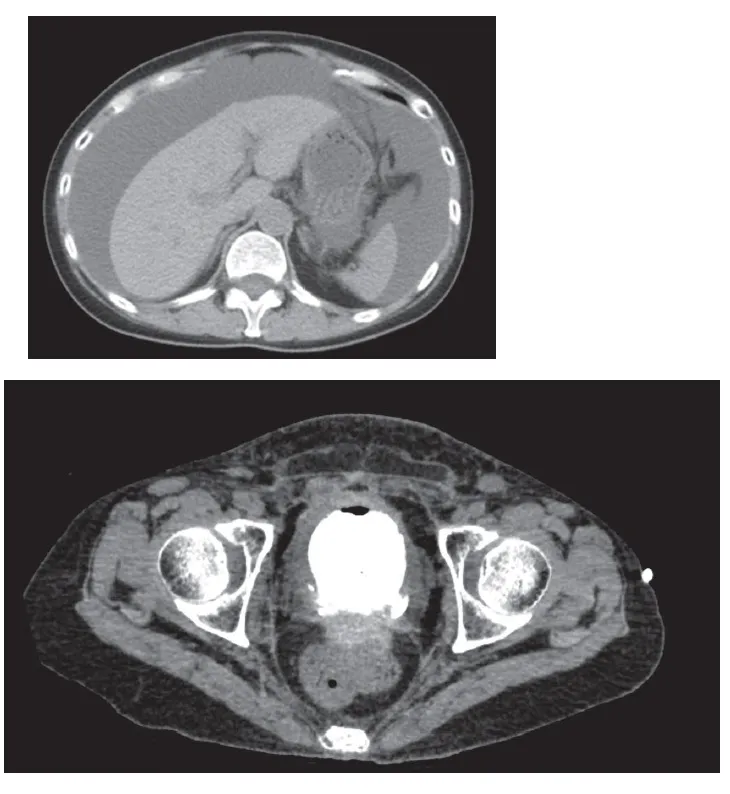

Foi realizada uma tomografia computadorizada do abdômen, sendo identificado uma área de perfuração na parede

posterior-esquerda da bexiga, sugerindo uma ruptura da bexiga. A paciente foi diagnosticada uma perfuração vesical, com fuga de urina para a cavidade peritoneal (figura 2).

Figura 2. TC abdômen mostrando as ascite e vazamento de contraste na bexiga (lado esquerdo da parede posterior da bexiga).